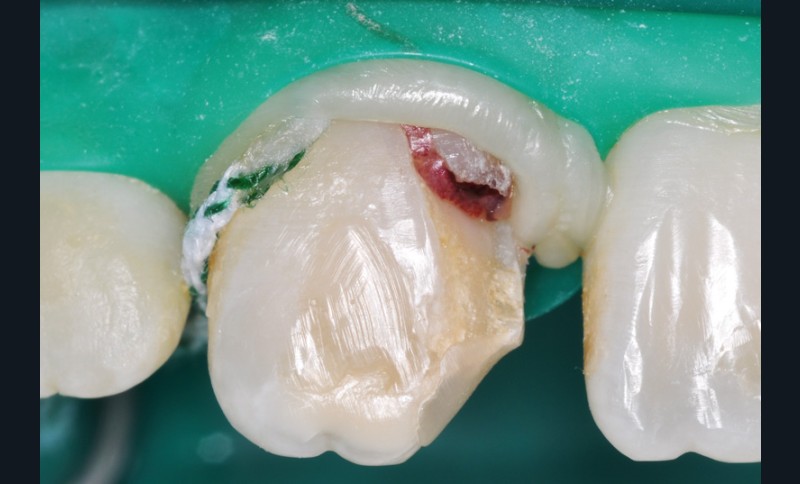

a à d Jeune patiente âgée de 8 ans, adressée suite à un traumatisme survenu 3 semaines auparavant, pour l’extraction de sa 21. La vue clinique montre un saignement ligamentaire, une mobilité coronaire et une fracture coronaire amélodentinaire longitudinale partant de l’angle mésial et se poursuivant en direction radiculaire sous-gingivale (a). Un test de vitalité positif indique que la dent est vitale, la radiographie permet de poser le diagnostic de fracture coronoradiculaire, et d’objectiver l’immaturité radiculaire (stade 8 de Nolla) (b). Une contention est mise en place et la plaie dentinaire coronaire est scellée au mieux par collage afin de limiter le risque d’une complication infectieuse (c). A 15 jours la dent est vivante et aucune complication n’est apparue (d). La patiente est revue après 3 mois pour déposer la contention, le test de vitalité est positif, et la radiographie de contrôle montre une apexogenèse en cours (e). Cependant la gencive s’est invaginée dans le trait de fracture (f). La zone est débridée sous microscope (g) puis scellée et reconstituée à l’aide d’un adhésif SAM et d’un composite fluide (h). Le contrôle radiographique à 6 mois est satisfaisant (i). Ce cas clinique illustre le fort potentiel des pulpes jeunes et du ligament alvéolodentaire à résister aux agressions et à assurer les fonctions dentinogénétiques et l’édification radiculaire.